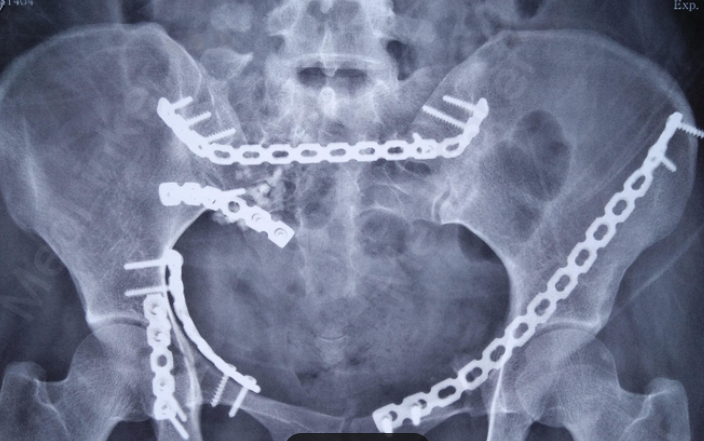

图1:切开复位内固定